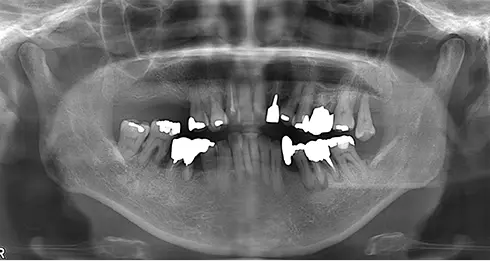

| 年齢/性別 | 70代女性 |

| 主訴 | 左下奥歯に痛みがある、全体的に治したい |

| 治療内容 | 全体的に歯周病やむし歯、根の治療を行い、仮歯を使用して咬合治療を実施。左上、右下、左下の計3本を抜歯し、右上には2本のインプラントを埋入しました。 |

| 治療期間 | 4か月(インプラントのみ) |

| 費用 | 1,116,500円税込 |

| リスク・副作用 | 炎症反応によって術後に腫れや副鼻腔炎が生じることがあります。その程度は、手術の範囲や方法によって異なりますが、多くの場合、時間の経過とともに徐々に治まります。 |